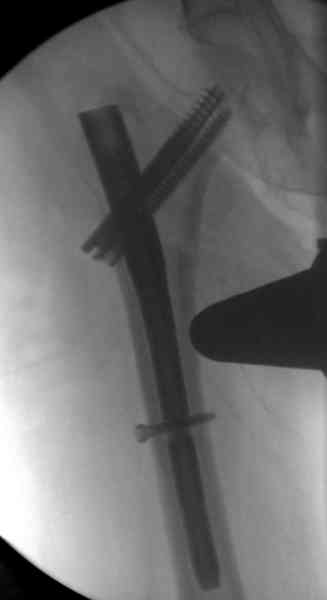

Мы получили испытательный вариант инструментария для пробы, хотя компания объявила, но ещё не для широкой публики, обещают к сентябрю. За полтора месяца, включая сегодняшнюю, вот уже восьмая операция по счету. Удобный инструментарий, ничего лишнего, научились делать быстро, посмотрим что будет, пока нравится.

Здесь сканнированные снимки импланта и операционные снимки больной.

На этом снимке процесс компрессии нижним болтом.